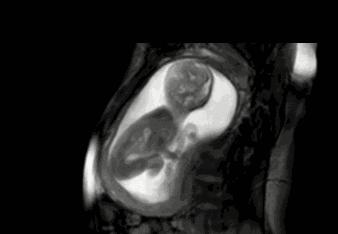

胎宝宝在子宫中,周围被羊水保护着,其实这个时候很大程度上,是 宝宝在妈妈肚子里面“游泳”呢。

有一些妈妈表示,感觉肚子里面像是有一条小虫子一样在游来游去,不过一些新手妈妈在感受胎动时不太确定。因为刚开始的胎动,跟平常肠蠕动的感觉很像,而且很多妈妈只能感受胎宝宝微弱的蠕动,所以孕妈妈不清楚这个感觉是不是宝宝在运动。

而且胎 宝宝此时的动作幅度应该不是特别的大,只是让妈妈的子宫壁感受到了变化 ,并没有让妈妈的肚皮有明显的感觉。